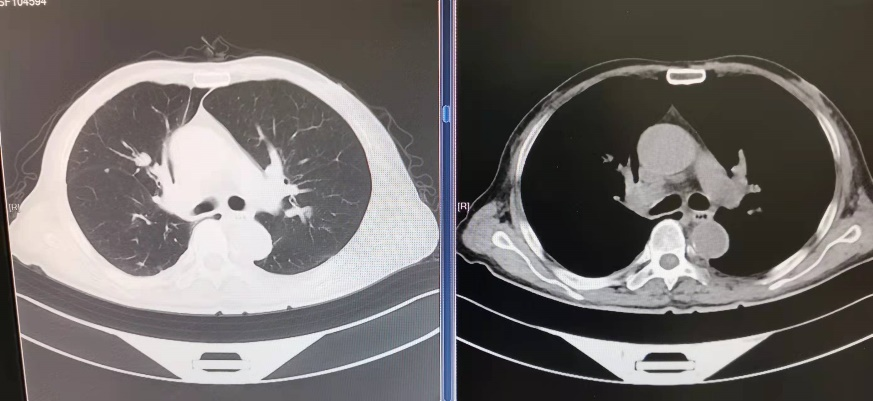

术后CT见梗阻解除,气道通畅

次日,吴先生已在手术室内完成全麻。术中,呼吸科、麻醉科和手术室医护互相配合,在硬镜下为病人进行气道内探查。硬镜下可见气管下段的新生物堵塞约90%的管腔,而右主支气管管腔已被完全堵塞。蒋主任团队在气管镜下对新生物进行圈套、切除,术中仅有少量出血,共取出3块新生物组织送病理检查,术后再次探查见气管、右主支气管管腔已恢复通畅。